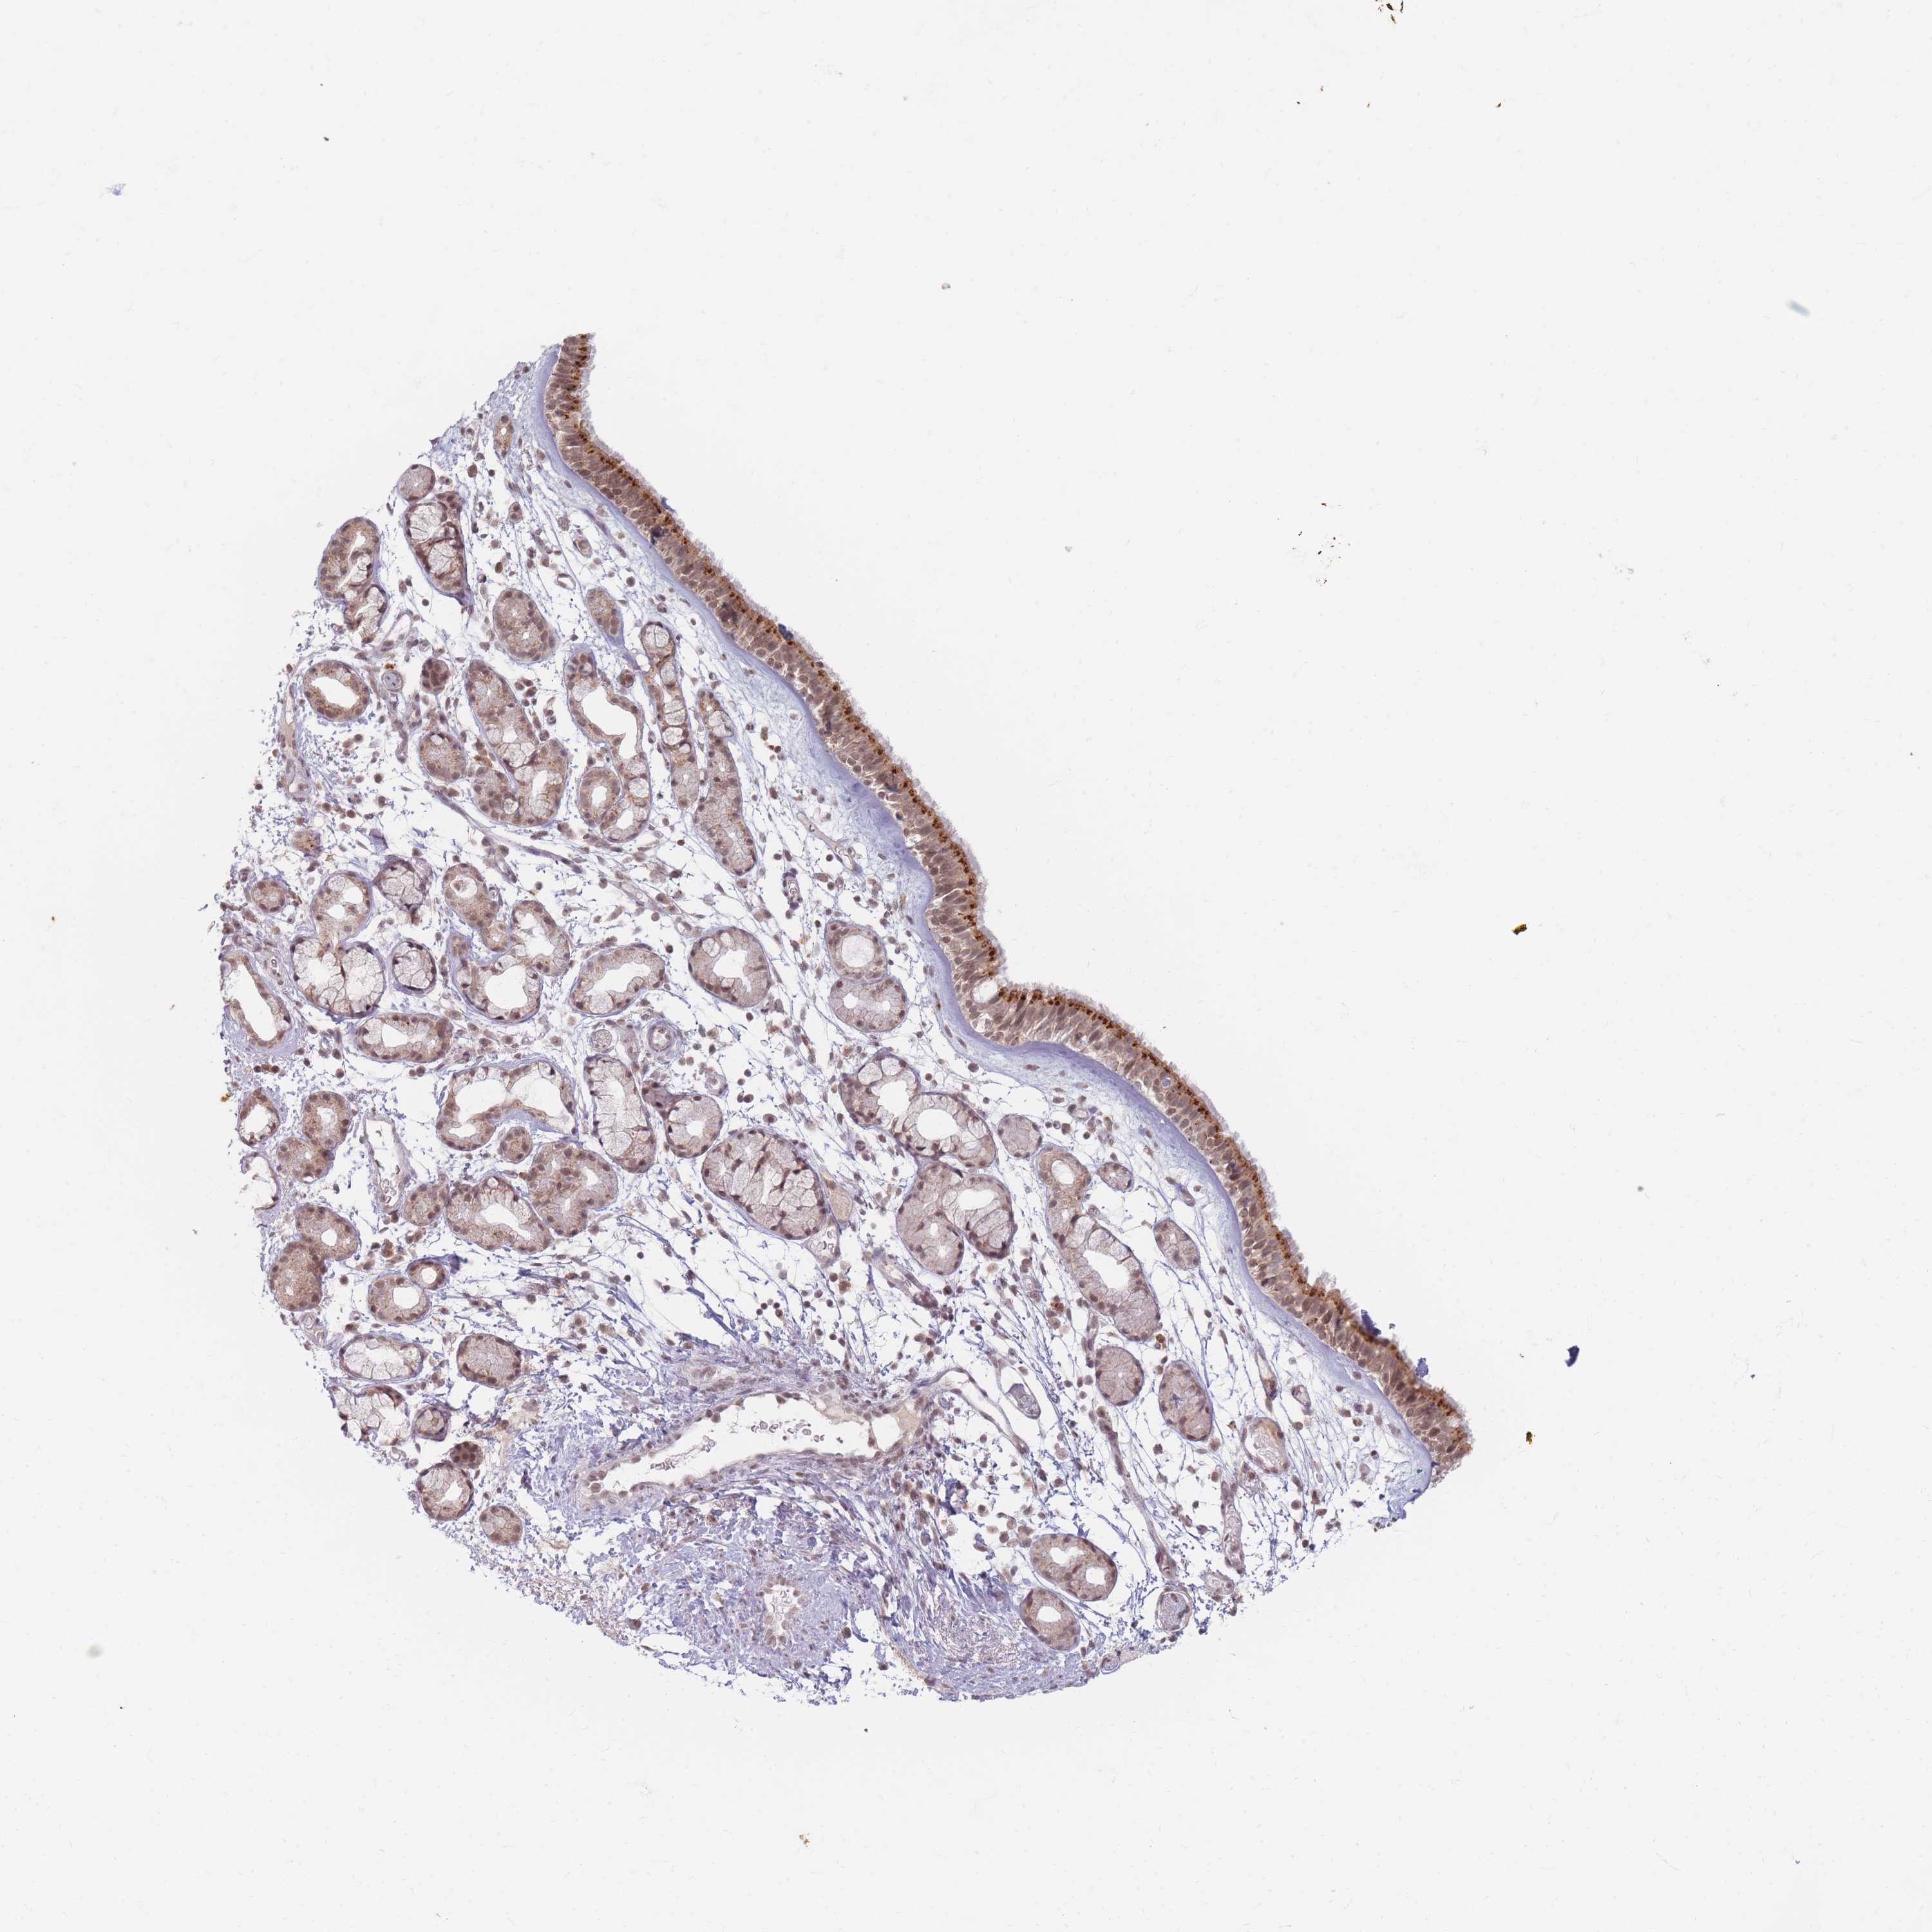

SPATA45